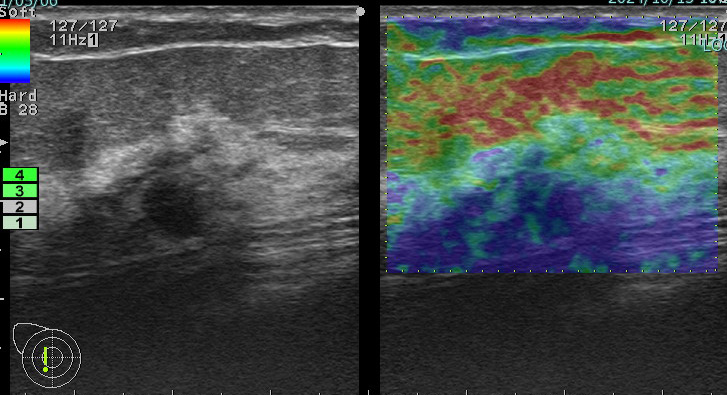

上に挙げた4つのエラストグラフィー

これが何を物語っているか?

エラストグラフィーは何か所見があった際に「これは怪しい!」と思わない限り追加で行わないものです。

これを実は4回も(昨年)行っていたのです。

つまり、(昨年も)その技師は「明らかに癌を疑っていた。」

この4枚のエラストグラフィーは技師の「これは怪しい所見です!是非要精査にしてください!」という心の叫びと言えるんだね!

まさに、その通り!

ただ、悲しいかな。技師さんのその「必死な思い」は、検診画像評価を行う医師には伝わらなかった。